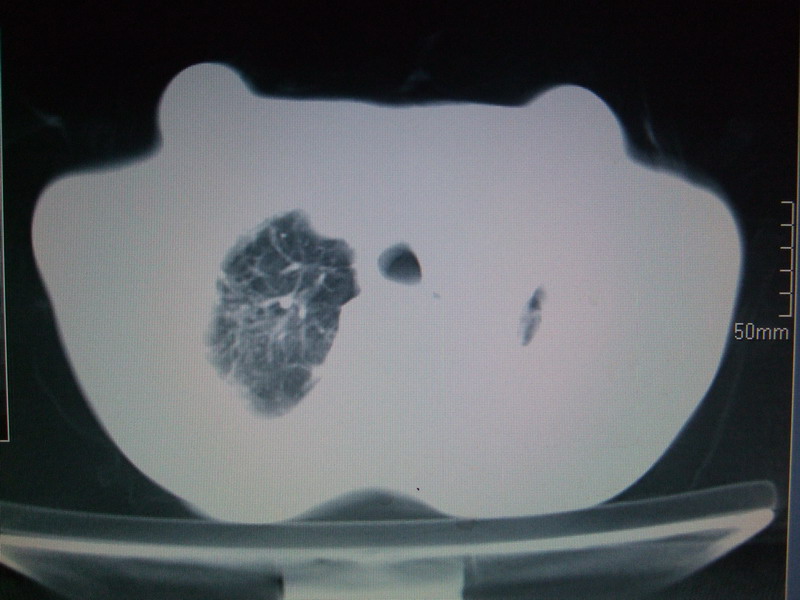

男  70岁,发烧咳嗽4天。盗汗,消瘦。无痰中带血丝,以前有肺tb病史,ct见,双肺tb,左侧胸廓塌陷,左胸膜肥厚粘连。纵隔移位,右侧胸腔积液,大家说说那个心影前左肺舌叶除了肺大炮还有炎症还是干酪性肺炎?有占位吗?我看纵隔淋巴结也大。

双肺继发性肺结核伴部分左肺毁损!

1)两肺继发性肺结核并左肺上叶肺不张,支气管扩张。2)双侧胸膜炎(胸膜增厚+少量胸腔积液)。